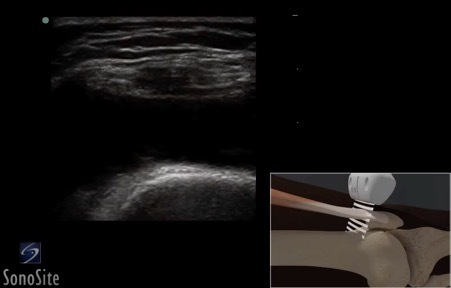

Knee Joint Injection 1 Image